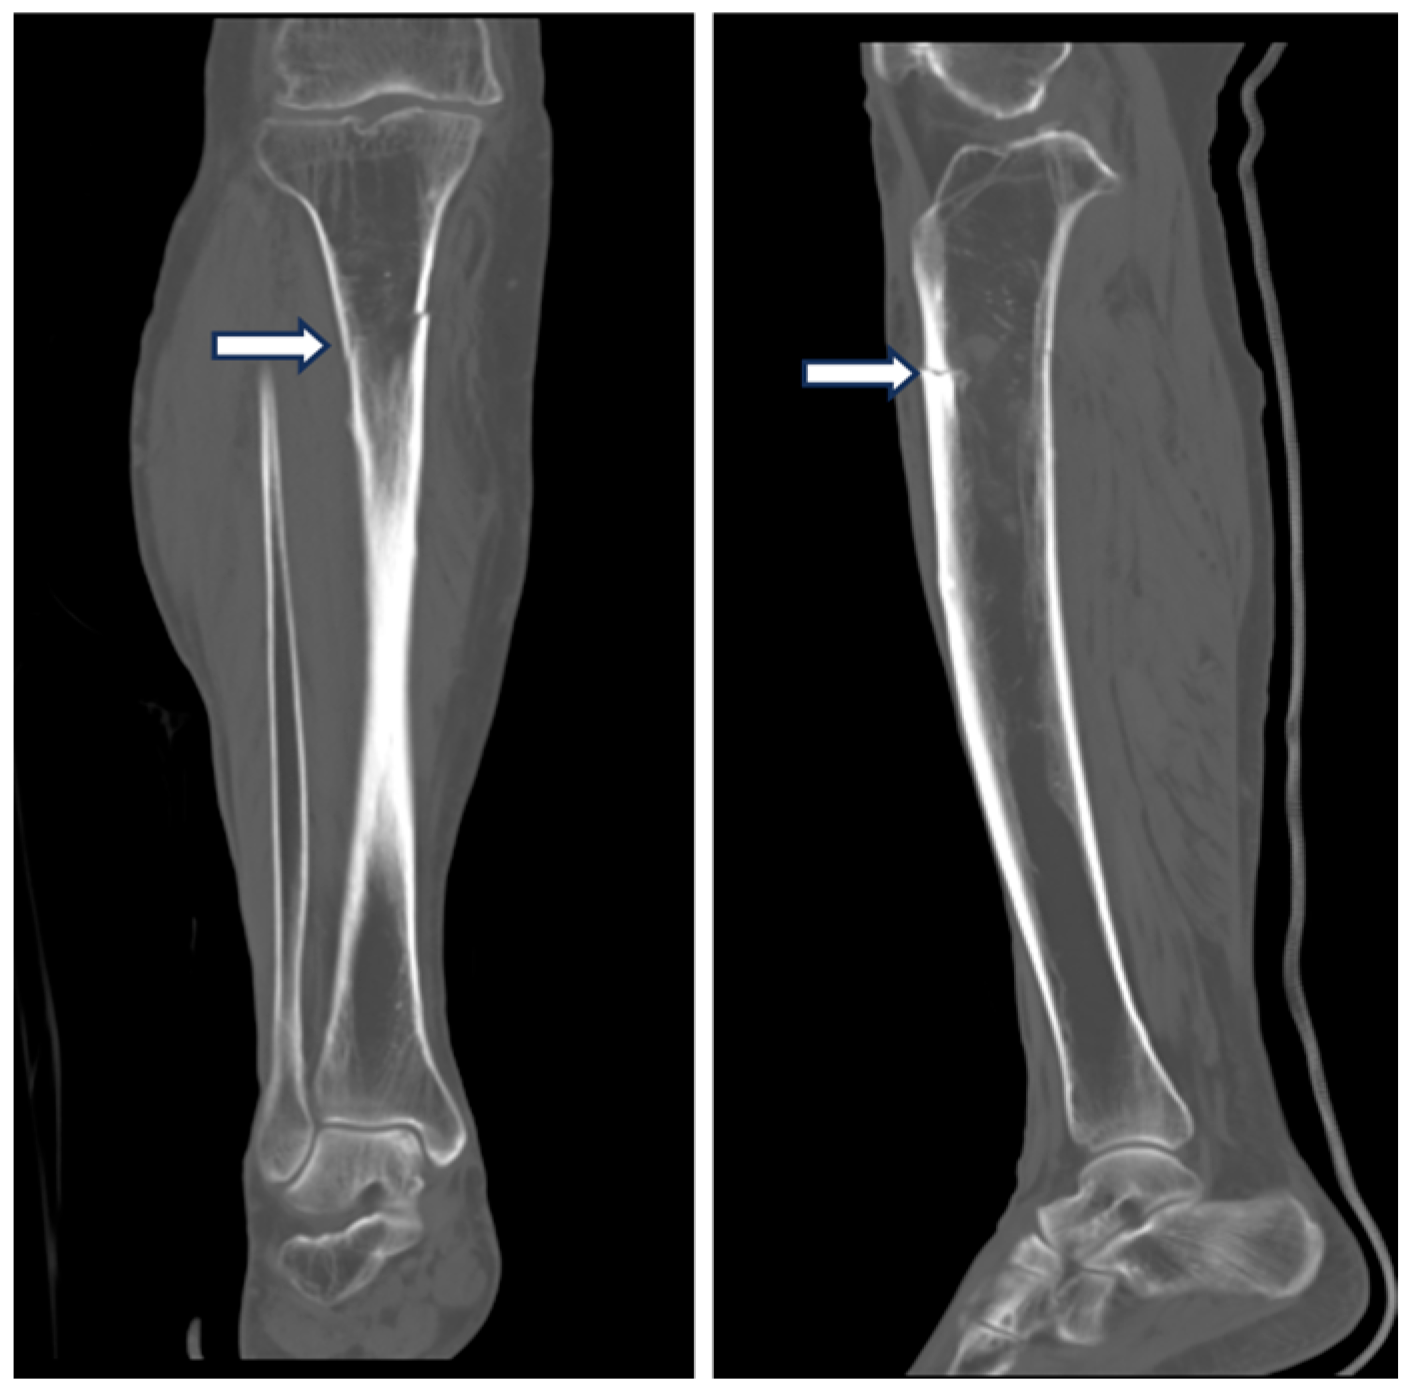

2. Case Presentation